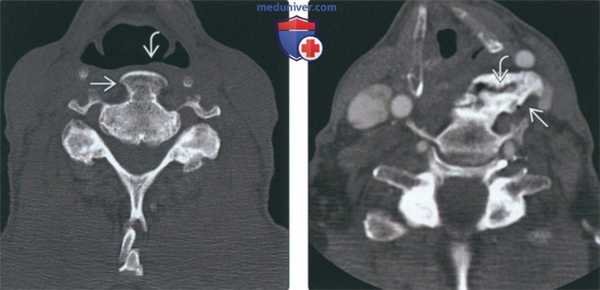

(Слева) На аксиальной КТ без КУ у пациента с ДИСГ визуализируется крупный вентральный остеофит с кортикальной пластинкой, оказывающий воздействие на гортаноглотку. При существенном воздействии возможно появление симптоматики.

(Справа) На аксиальной КТ определяется массивная оссификация со смещением левой сонной артерии и воздействием на гортаноглотку слева. Расщелина в оссификате на уровне межпозвонкового диска - частая находка. Возможна сопутствующая дисфагия, обусловленная не только механической обструкцией пищевода, но и воспалением и фиброзом.